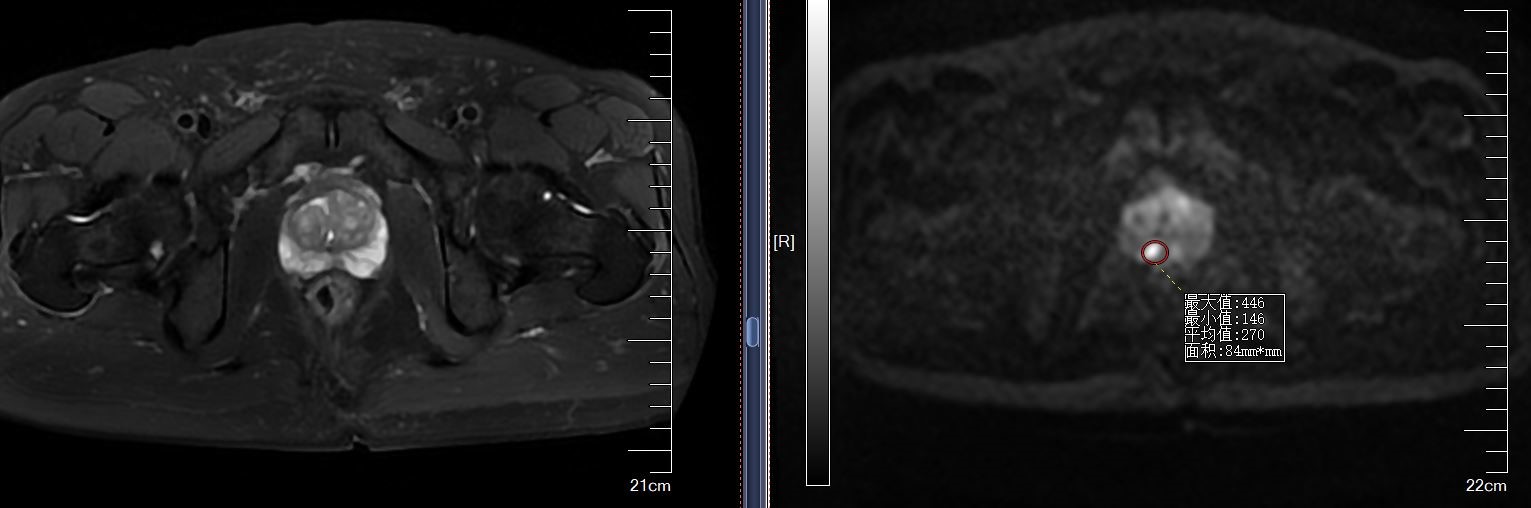

mpMR-TURS融合穿刺(RVS)是指将患者已出结果的核磁(MRI图像)与经直肠超声图像(TURS)融合,在超声实时引导下,对核磁可疑靶点进行精准导航穿刺,将CT/MRI的高度敏感性与超声的实时性联合应用。

我院已成功开展病例,患者张大爷因“体检发现PSA升高一周”入院,前列腺特异性抗原升高,入院后完善磁共振提示前列腺右侧外周带异常信号影,行多影像融合介入导航术。

术前拷贝该患者核磁数据并导入机器中,经过核磁病灶定位,超声图像显示,匹配对位后,实施前列腺穿刺术,手术共用时12分钟,共穿刺14针,常规穿刺12针,核磁可疑病灶区追加2针。手术过程顺利,患者术后无明显不适,术后病理提示为前列腺癌。